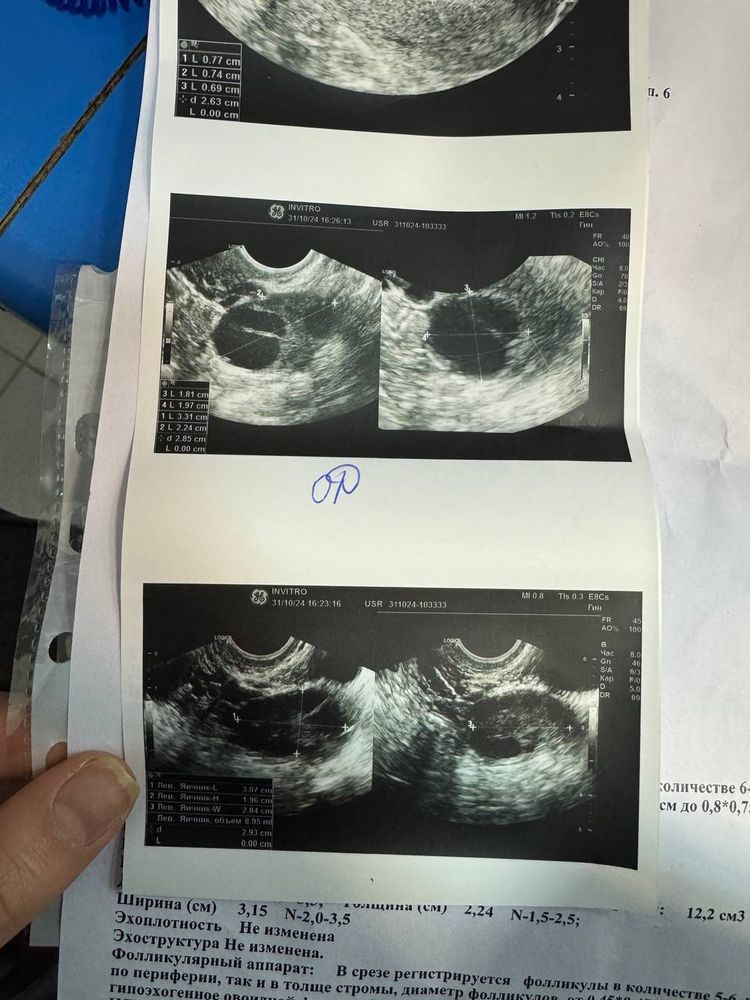

Tatiana, я ходила на узи на 17ДЦ и у меня было ЖТ но врач сказал, что овуляция была примерно два дня тому назад. А я думаю что в этот день была Изображение Изображение

Была на УЗИ, был фолликул, приехала на УЗИ через 2 часа, было жёлтое тело

я была на узи видимо сразу после О, узист сказала, что уже ореола появляется, значит несколько часов назад. значит на хорошем аппарате хороший узист увидит чуть ли не в тот же день